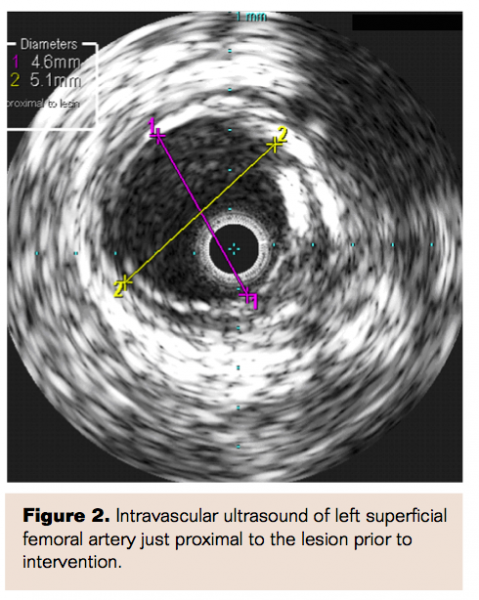

Upon angiography, the left common femoral, profunda femoral, and superficial femoral (SFA) arteries were all patent proximally. By the mid-thigh, heavy calcification resulted in significant stenosis and plaque burden of the SFA with the greatest degree of stenosis at Hunter’s canal (at least 90% diameter stenosis) (Figures 1 and 2). The popliteal artery, anterior tibial artery, and posterior tibial arteries were patent.

Intravascular ultrasound (IVUS) confirmed the size, extent, and length of the plaque. Stenting of this lesion thus required two Zilver PTX (Cook Medical) stents. A 6 mm x 80 mm stent was placed in the distal SFA, and a 7 mm x 80 mm stent was placed just proximal to the first. The stents were post-dilated with a 6 mm angioplasty balloon with an excellent angiographic and hemodynamic result (Figure 7). Completion hyperemia measurements showed a pressure gradient of 1 mmHg and a ratio of 1.0 (Figure 8, Table 1).